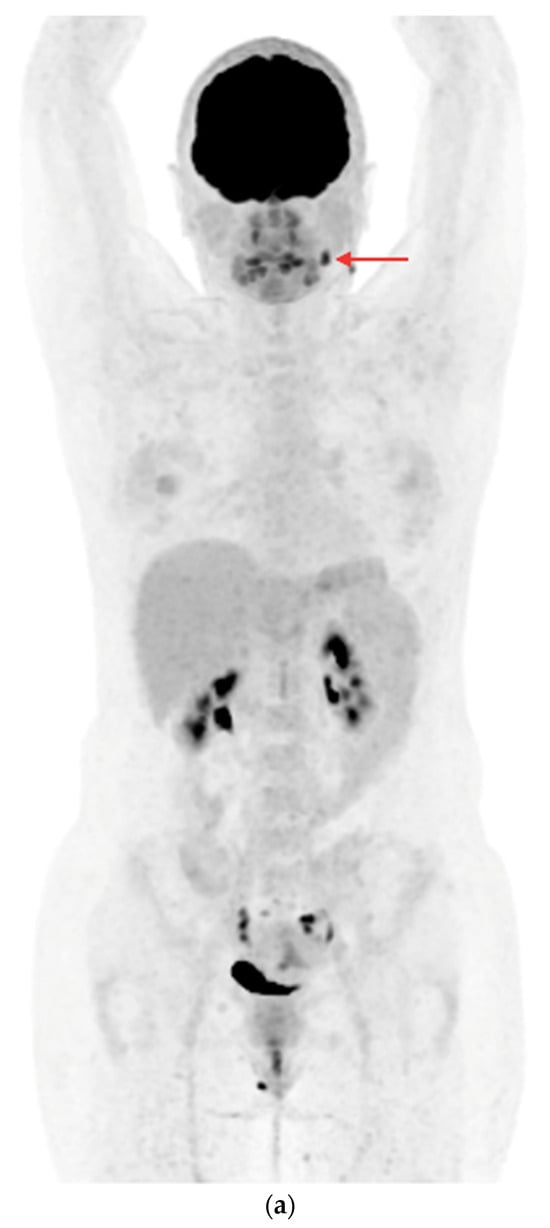

- In the case of potentially resectable lesions, the lesions were operated on after the FNA verification (Figure 3a,b).

Figure 3. PET/CT with [18F]FDG (a) Maximum-intensity projection (MIP). (b) Axial fusion projection. These show an example of the accumulation of the [18F]FDG in the left cervical lymph node (red arrow). The lesion was verified as being metastasized DTC using FNA and resected. The preoperative sTg concentration was 5.55 ng/mL. In the postoperative follow-up, the sTg concentration decreased to being undetectable (<0.04 ng/mL). - -